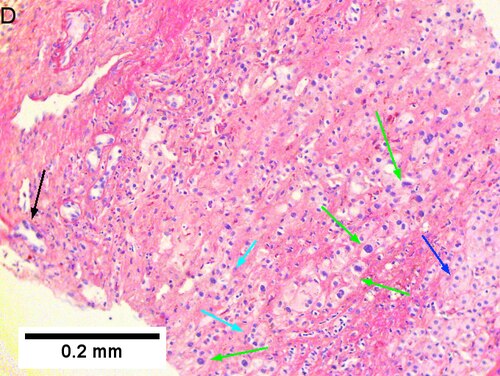

Cholangiocarcinoma, intrahepatic, with associated abscess. A. Aberrant spaces (arrows) contrast with the scar to the regions left and, at right, hemosiderin laden macrophages amid granulation tissue [40X]. B1. Disorderly spreading glands (black arrows) associated with atypical single cells (cyan arrows) have nuclei that contrast with those of the normal bile duct (blue arrow) with its associated artery (green arrow) [200X]. C. PAS without diastase shows disorderly spreading, aberrantly shaped glands at left (arrows) and red degenerated hepatocytes to right [200X]. D. PAS with diastase shows proliferating bile ducts to left, one with highly aberrant nuclei (black arrow), highly atypical cells at middle (green arrows) with sometimes incomplete (cyan arrows) acini, and normal liver at right (blue arrow) [200X]. E. CK7 immunostain shows proliferating glands at left and a disorderly spread of single cells and cell groups at right, amid hepatocytes [200X]. F. CK7 immunostain at higher power shows the stained cells have aberrant nuclei [400X].